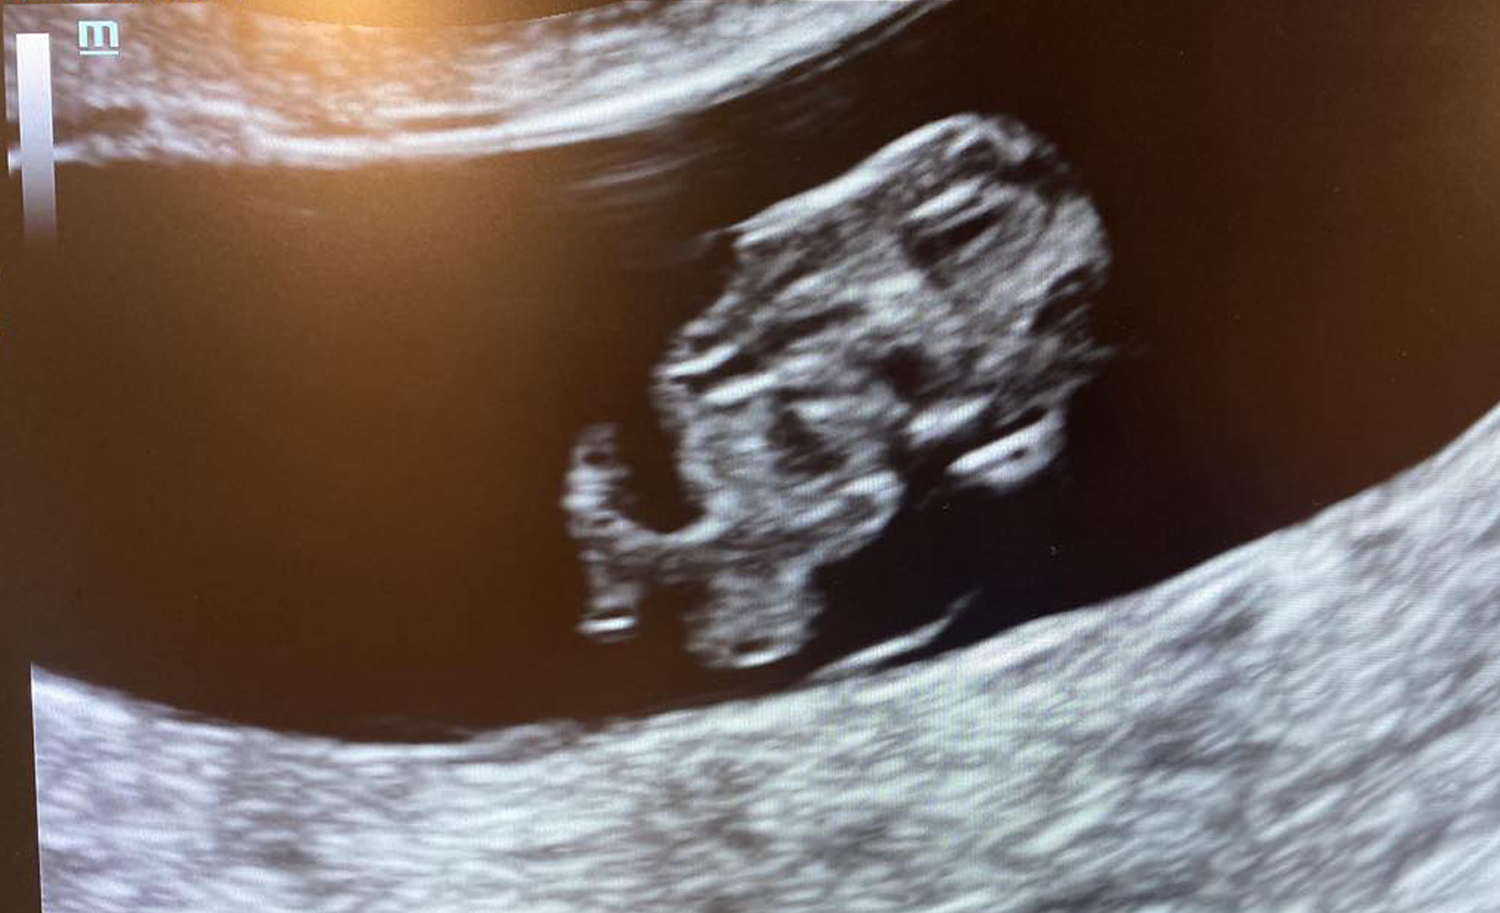

“Once she arrived, she went straight to the ultrasound, her one-year-old baby girl in tow,” she said. “On the screen, (there was) a healthy, thriving six-week baby, and, music to their ears, a strong heartbeat coming from the doppler.”

“An eight-week, one-day healthy, happy, and thriving baby danced on the screen!” Ancell said.